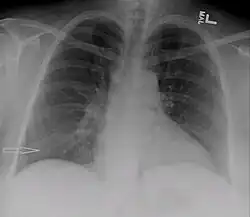

| Right sided pleural effusion caused by urinothorax | |